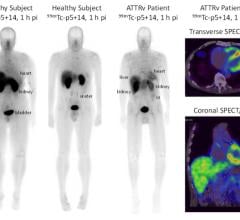

Computed tomography (CT) and magnetic resonance imaging (MRI) have been used for years to rule out other causes of dementia. More recently, positron emission tomography (PET) and cerebral metabolism using fluoro-deoxy-D-glucose (FDG) have been used to show characteristic changes in the brain and help rule in Alzheimer’s pathophysiological processes.

In April the U.S. Food and Drug Administration (FDA) approved Avid Radiopharmaceuticals’ (now part of Eli Lilly) Amyvid, a brain plaque diagnostic tool using florbetapir (F-AV-45). This radiotracer agent is delivered intravenously and is drawn to beta-amyloid plaque, a characteristic of AD. This allows a physician to see accumulations of amyloid in the brain, which in turn help the physician to determine whether a patient is suffering from some form of dementia, but cannot confirm a diagnosis of AD. Other diseases such as Parkinson’s disease, Huntington’s disease and Creutzfeldt-Jakob disease characteristically present with plaques as well, therefore physicians must still use mental and behavior cues to diagnose a patient with AD.

Amyvid’s half-life is close to 110 minutes, compared to the previously used radiotracer known as PiB (Pittsburg compound B [fluorescent analog of thioflavin T]), which offered a half-life of only 20 minutes. A longer half-life means more time allowed for the physicians to perform the injection and analysis of a patient. Unfortunately, the downside to using florbetapir is its high cost and patient exposure to radioactive material.

Amyvid is the only FDA-approved diagnostic PET tracer for imaging plaques in vivo, but there looks to be another agent in the pipeline that could potentially provide more diagnostic armament for detecting AD. Navidea Biopharmaceuticals’ AZD4694 Fluorine-18 labeled dye has completed Phase IIa clinical trials, and Phase III clinical trials will likely begin in 2013. This entity has been shown to be highly sensitive in detecting amyloid plaque. The signal-to-noise ratio remains low due to low background and white matter uptake, thus providing clear images of amyloid plaques. Navidea hopes AZD4694 will be used as an early identification tool for AD.